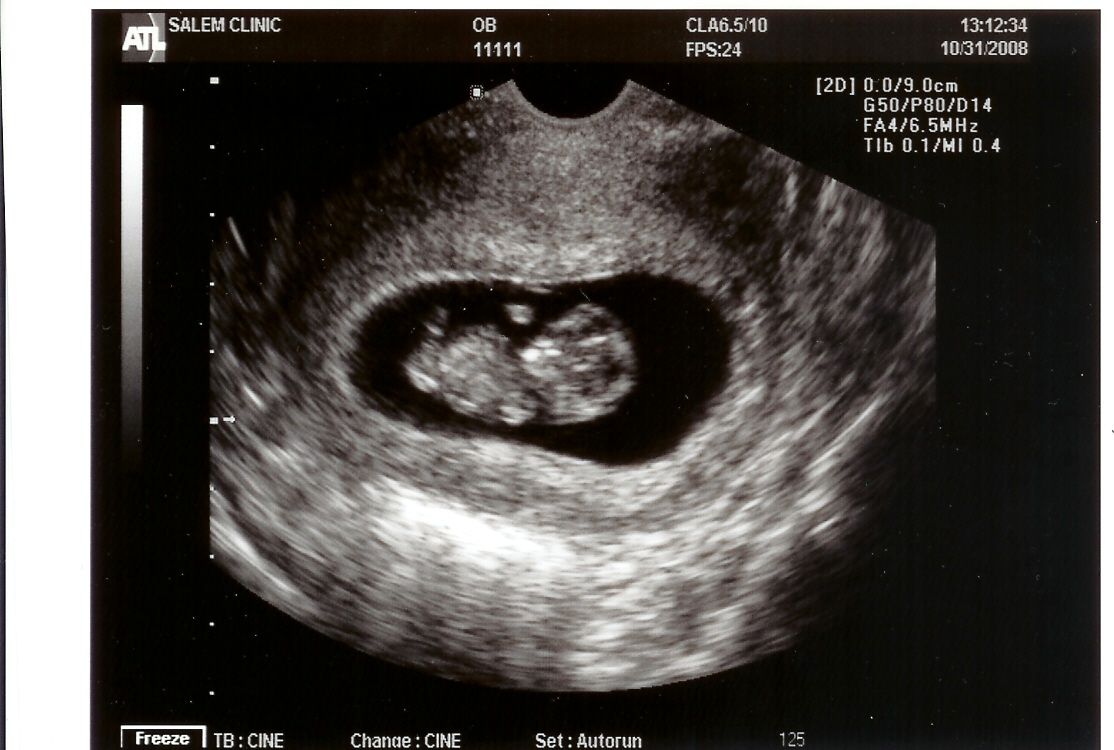

Ультразвук 8 недель беременности

Примерно в это время вы можете пройти первое дородовое обследование (также известное как прием на 8-недельную беременность), и если вы это сделаете, то сможете мельком увидеть свой 8-недельный плод на УЗИ.Подскажите ауууууууууууууууууууууууууууууууувууууууууууууууууууууууууууууууууууууууууууууууууууууууууууууууууууууууууусууууууууууууууууууууууууууууууууууууууууууууууууууууууууууууууууууууу ручкам и ножкам малышу. Вы еще не можете этого почувствовать, но это действительно происходит!

На 8 неделе беременности пальцы рук и ног ребенка теперь только слегка перепончатые, а хвост (да, был) исчез. Интересный факт: вкусовые рецепторы ребенка формируются, готовясь к первому приему пищи. Приготовьтесь обсудить несколько 8-недельных ультразвуковых изображений, которые вы должны получить на этом первом визите.

УЗИ эмбриона на 8 неделе беременности.